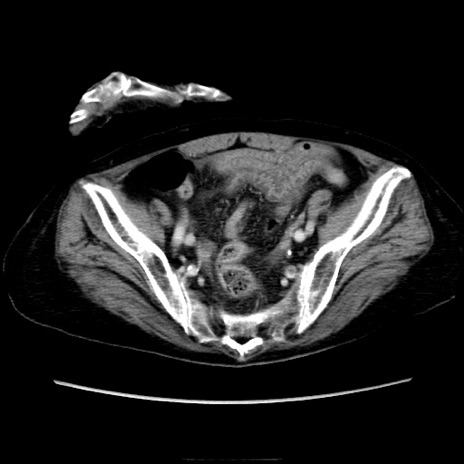

症例40(横断像)

横断像